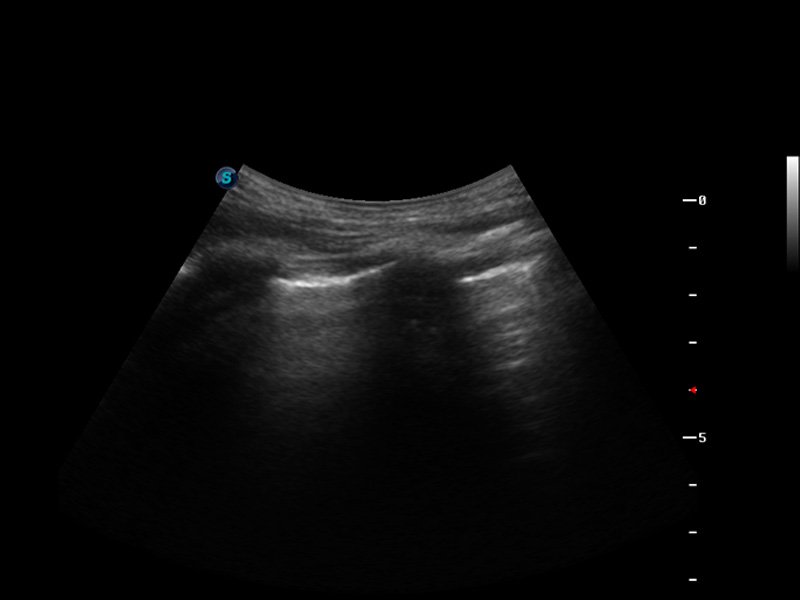

S9便携式彩色多普勒超声诊断仪是银河集团官网研发的高端便携彩超设备,外观设计新颖、产品性能卓越。S9在便携超声领域采用了突破传统的触摸屏交互设计,并以先进的软件硬件技术和设计理念,为您带来清晰的图像质量、稳定的工作性能和便捷的操作体验。